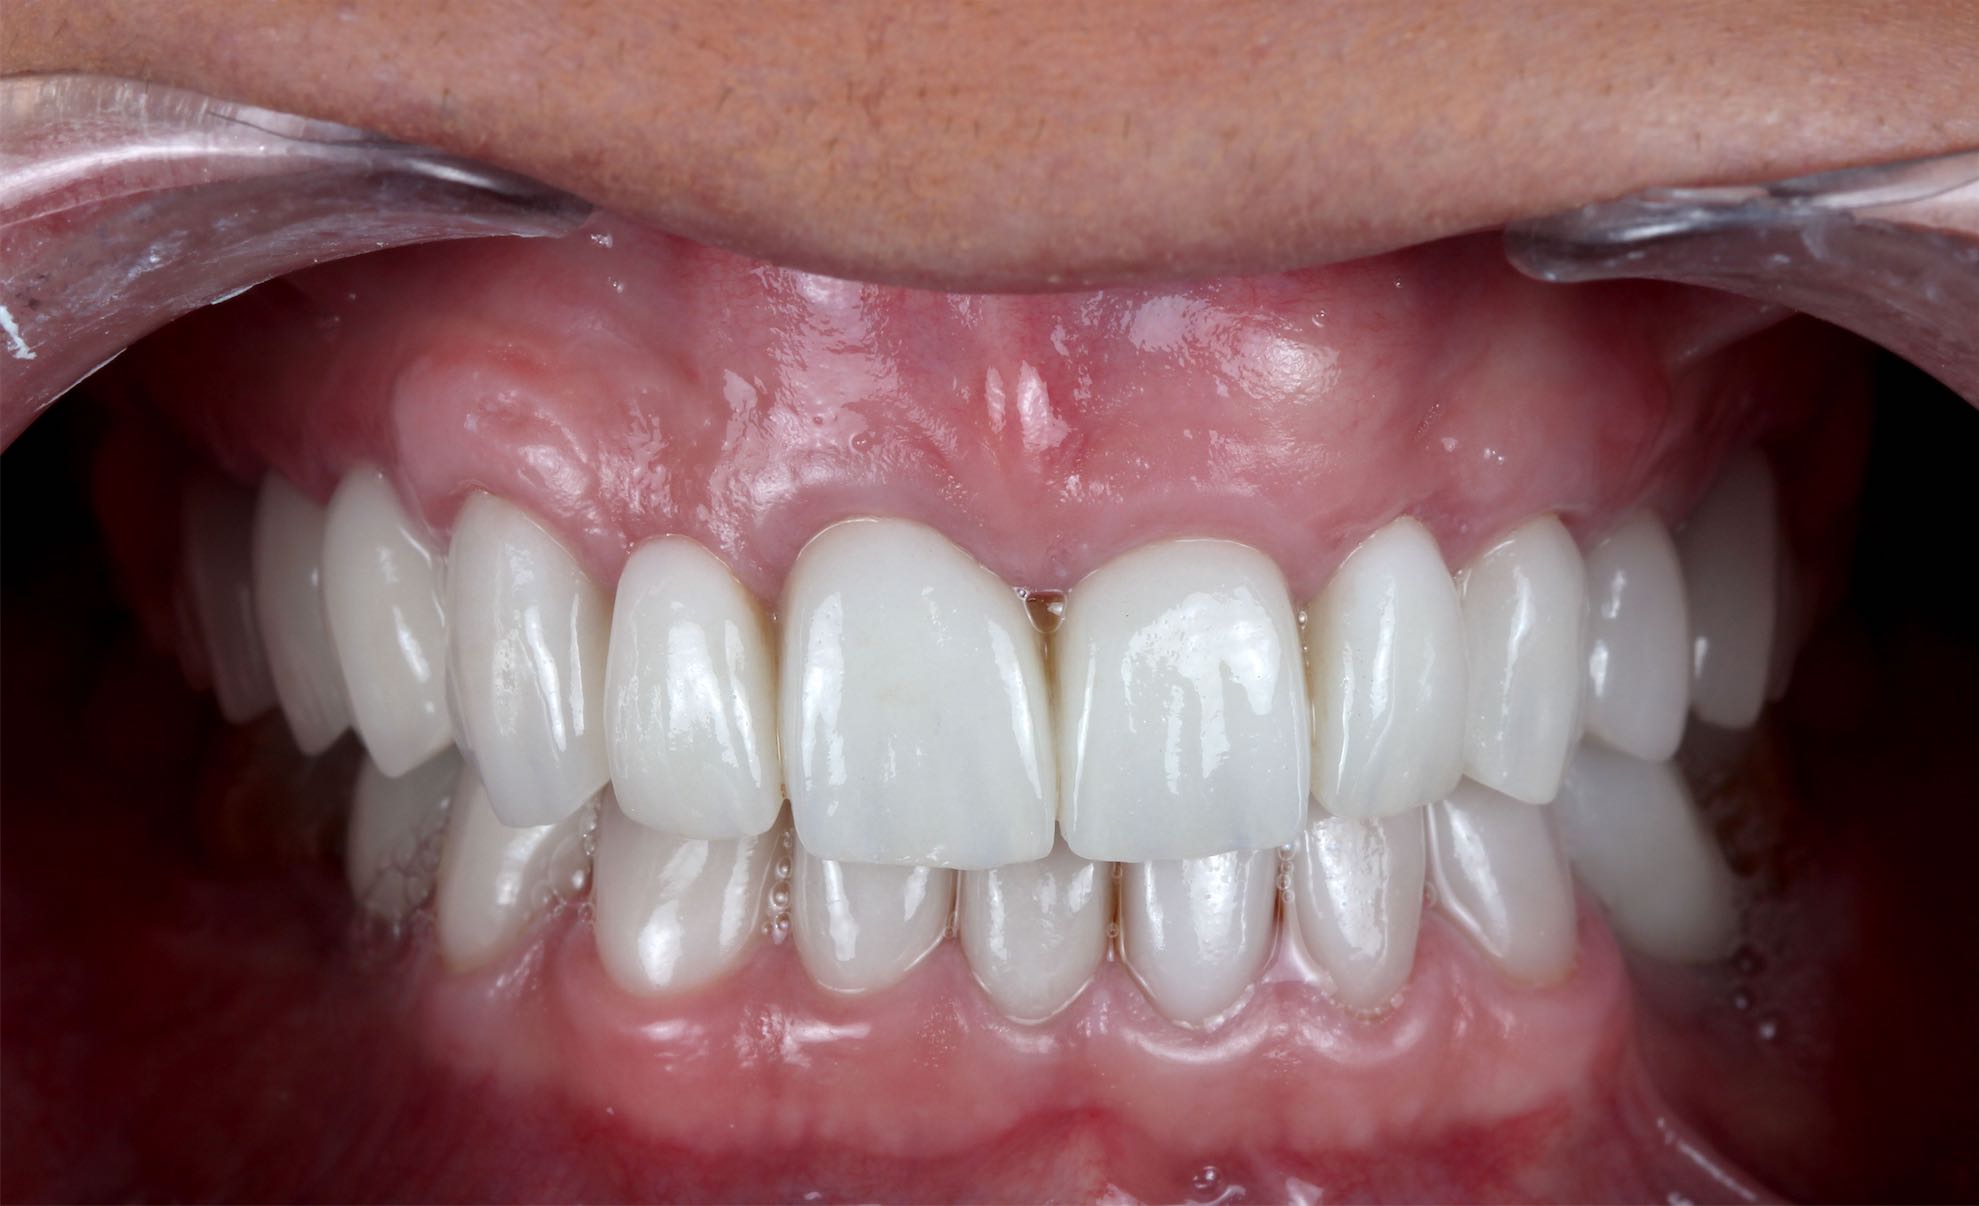

Odontología Estética. Coronas

BeforeAfter